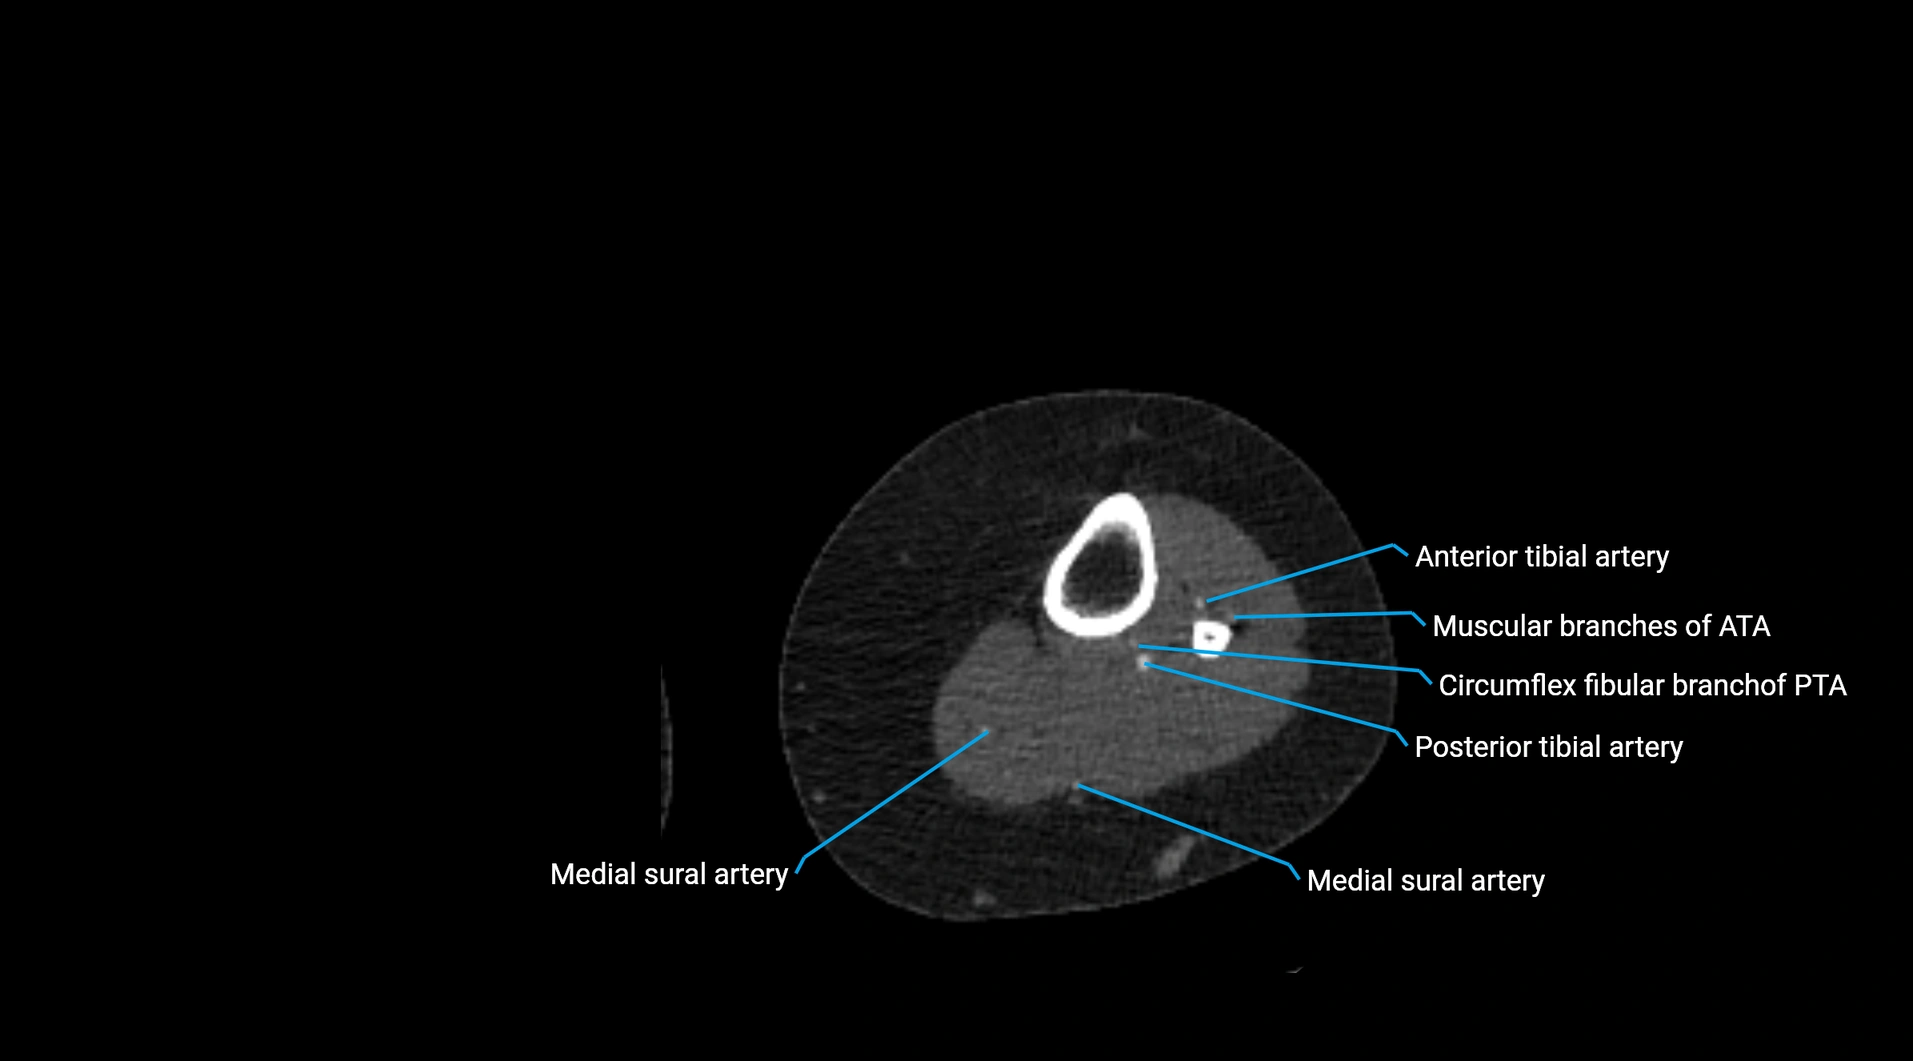

CT images

image

Contrast-enhanced CT (CTA):

• Gold standard for abdominal aortic imaging

• Provides excellent detail of lumen, wall, aneurysm, thrombus, and branch vessels

• Multiplanar and 3D reconstructions help in aneurysm measurement, stent graft planning, and dissection evaluation